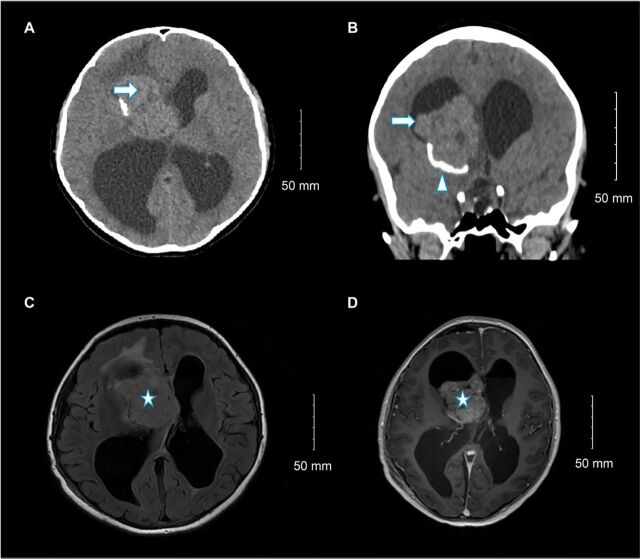

脐下巨细胞星形细胞瘤(SEGA)是一种罕见的环形星形胶质瘤,约占结节性硬化症(TSC)病例的25%。在此,我们将讨论 SEGA 的一种非典型表现,包括遗传改变、对临床表现的影响以及每种药物和手术治疗方案的决定因素。一名14岁的女孩因间歇性头痛和右侧脑室内肿块(起源于门罗孔附近)而就诊。由于肿瘤靠近重要结构,必须进行最大限度的安全切除,这才改善了她的症状。组织学检查结果显示她患有SEGA,基因测序显示她有TSC2基因突变。然而,完整的临床和放射学评估未能发现 TSC。两个月后,偶然发现了一个新的蝶鞍下结节。她的左枕角病变复发,弥漫性平滑脑膜强化,无脊柱下垂转移。由于肿瘤无法切除,她接受了依维莫司治疗。随后的影像学检查显示,残留病灶和新发病灶均有所减少。

Subependymal giant cell astrocytoma (SEGA) is a rare circumscribed astrocytic glioma that occurs in approximately 25% of all tuberous sclerosis (TSC) cases. Herein, we discuss an atypical presentation of SEGA, including the genetic alterations, impact on clinical presentation, and the determinants of each medical and surgical treatment option. A 14-year-old girl presented with intermittent headache and a right intraventricular mass originating near the foramen of Monro. The tumor's proximity to critical structures necessitated maximum safe resection, which improved her symptoms. Histological findings indicated SEGA, and genetic sequencing revealed a TSC2 mutation. However, complete clinical and radiological evaluations failed to reveal TSC. Two months later, a new subependymal nodule was incidentally found. She had a recurrent left occipital horn lesion and diffuse smooth leptomeningeal enhancement with no spine drop metastases. She was administered everolimus as the tumor was considered unresectable. Subsequent imaging revealed a reduction in both residual and new lesions.